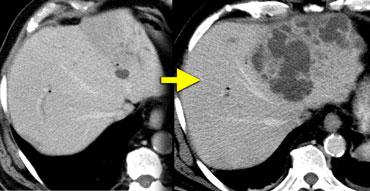

Ngấm thuốc lấp đầy dần (Progressive fill in)

Trước tiên hãy quan sát các hình ảnh bên trái và mô tả những gì bạn thấy. Sau đó tiếp tục đọc.

Tổn thương này chắc chắn có một số đặc điểm của u máu như ngấm thuốc dạng nốt trong thì động mạch và ngấm thuốc lấp đầy dần trong thì tĩnh mạch cửa và thì cân bằng.

Tuy nhiên, trong thì tĩnh mạch cửa, mức độ ngấm thuốc không sáng bằng mức độ ngấm thuốc của tĩnh mạch cửa.

Kết luận phải là tổn thương này không tương đương hồ máu ở tất cả các thì, do đó không thể là u máu.

Vì vậy, ngấm thuốc lấp đầy dần là một đặc điểm không đặc hiệu, có thể gặp trong nhiều tổn thương khác như di căn hoặc các khối u gan nguyên phát như ung thư biểu mô đường mật.

Sự ngấm thuốc thì muộn trong tổn thương này là do mô xơ trong ung thư biểu mô đường mật và là đặc điểm đặc trưng của các khối u này.